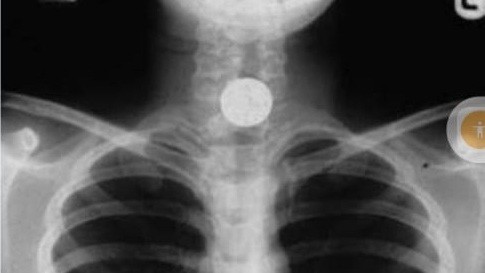

В Ат-Башы из пищевода 8-летнего ребенка извлекли 5 копеек СССР